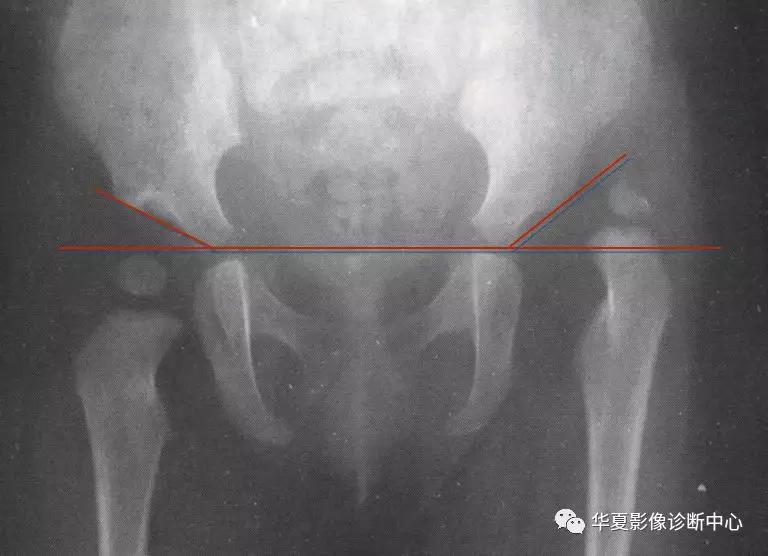

6. Shenton线:

正常闭孔上缘弧形线与股骨颈内侧弧形线相连在一个抛物线上,称为Shenton线,髋脱位、半脱位病例,此线完整性消失。

7.外侧线(Calve线)

外侧线(Calve线)即髂翼的外侧面与股骨颈外侧面的弧形连线,正常为连续的。